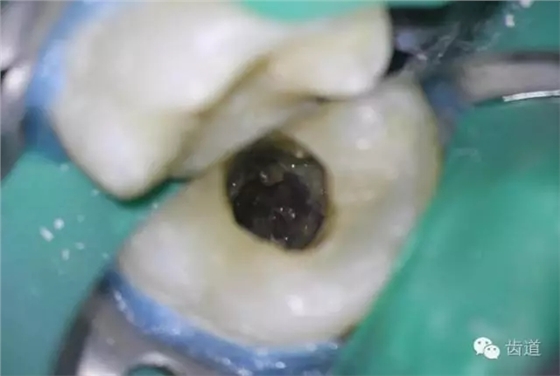

4. 初步開髓

5. Endo-Z揭全髓室頂

6. 可見髓腔內(nèi)壞死牙髓組織,無滲出

7. 3%次氯酸鈉浸泡髓腔5min